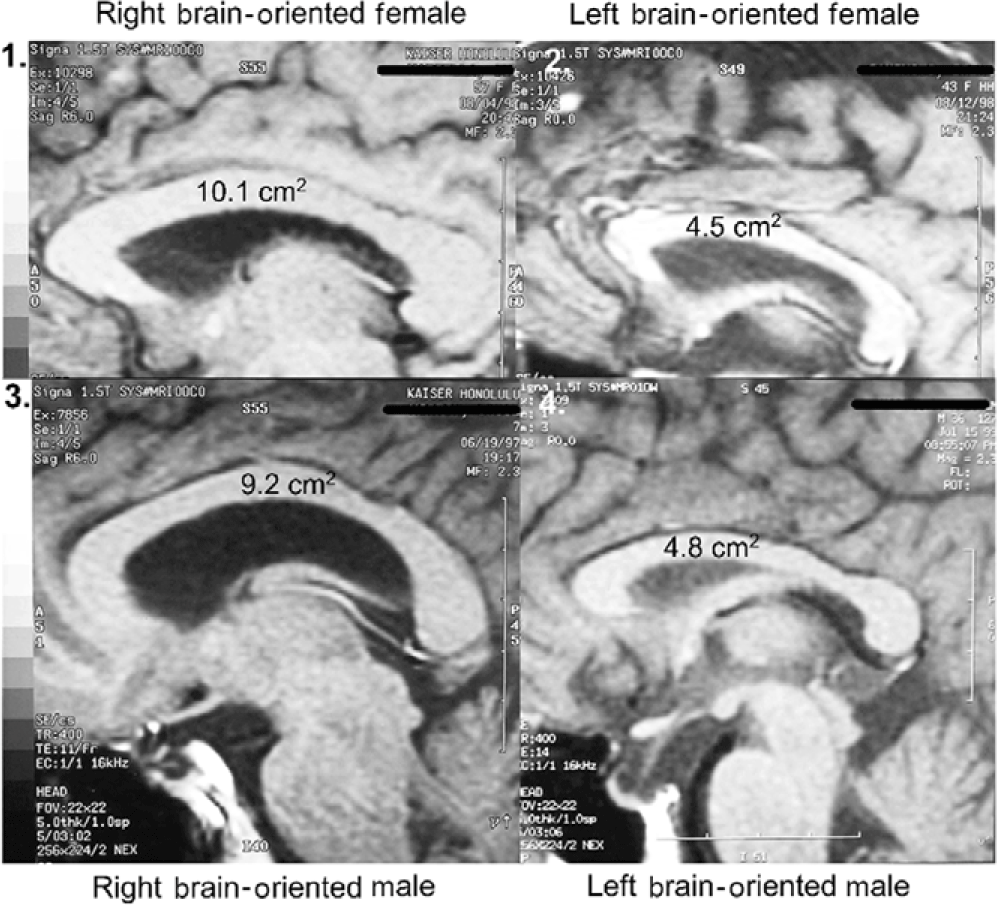

MRI assessments employed a General Electric Signa 1.5 Tesla MRI instrument. A midsagittal plane setup calibration protocol was run for 3 minutes using a T1 weighted spin echo sequence (TR = 400 msec, TE = 1/Fr) to image 5 mm slices from the midline plane and two adjoining sagittal planes 6 mm on either side. Whole-head photographic images were prepared from these three planes, and additionally, a 2.3x enlargement of the most medial plane, centering on the corpus callosum (CC). These four exposures were printed on a single 35 cm x 43 cm film sheet for each subject.

Sagittal corpus callosal cross-sectional areas were determined by tracing the corpus callosal outline of the 2.3x midline enlargement upon computer printer paper (Weyehauser 1180, 20 lb stock) of predetermined weight per unit area. The 8 ½ x 11 inch pages varied in weight by +/- 0.6%. Corpus callosal cutouts weighed on a microbalance varied in weight by +/- 35%. These data were converted to absolute CC cross-sectional areas by use of predetermined magnification and paper weight constants. Subject corpus callosal areas ranged from 4.5 to 10.1 cm2.

1.4.2 MRI assessment of ACC laterality (hemisity primary standard)

MRI assessments (Morton & Rafto, Reference Morton and Rafto2010) were obtained employing a General Electric Signa 1.5 Tesla MRI instrument. A midsagittal plane setup calibration protocol was run for 3 minutes to image 5 mm thick slices from the midline plane and two adjoining sagittal planes 6 mm on either side. Whole-head photographic images were prepared from these three planes. These three exposures were printed on a single film sheet for each subject. This procedure enabled both cortical walls on either side of the midline fissure to be visualized and measured, thus allowing sub-element lateralities of the ACC to be evaluated directly from the film. At two ACC sites on each side of the brain, one in Area 24 and the other at Area 24’ (Vogt et al., Reference Vogt, Nimcheniski, Vogt and Hof1995), estimations of the relative thickness of the ventral gyri (vgACC) there were made. This abbreviation and these four ACC locations within Areas 24 and 24’ are not to be confused with the more frontal ventral region of the perigenual ACC. The vgACC locations where these relative thickness estimations were made are illustrated by the arrows in Figure 4. Two lines were extended outward perpendicularly from the inner edge of the CC, ending in one case at a more frontal point in Area 24 and in the other at a more dorsal point in Area 24’. Both points were in the plane of the cingulate sulcus and arbitrarily selected, based upon the sites in the region giving the largest vgACC thickness for each brain side involved. The average of these two lateral relative thickness estimates from the vgACC of each side was then used to determine upon which side of each subject’s brain the vgACC was thicker.

their cerebral hemispheres by about threefold. Using quantitative MRI, we found the midline CC area of 113 subjects was significantly correlated, not with handedness or sex, but with hemisity (Figures 1 and 2) (Morton, 2006). That is, right brain-oriented individuals of either sex had significantly larger CCs than left brain-oriented persons.

2.1.9 Discovery of the neuroanatomical basis of hemisity

As mentioned above, ACC asymmetry is present in humans (Morton & Rafto, Reference Morton and Rafto2010), one side being larger than the other in a seemingly idiosyncratic manner (Figure 4). The larger side was congruent with hemisity subclass. If it was larger on the right, the person was found to be a right brain-oriented dominant male or female. If the ACC was larger on the left, the subject was determined to be a left brain-oriented supportive male or female.

3.6 Correlation of ACC size laterality and hemisity subtype

The fortuitous finding of laterality size differences between the divided ACCs was the key unifying factor when it was discovered that the larger ACC side was very highly correlated with hemisity subtype. That is, RPs almost invariably had larger ACCs on the right and LPs on the left. This gave hemisity a neuroanatomical basis.